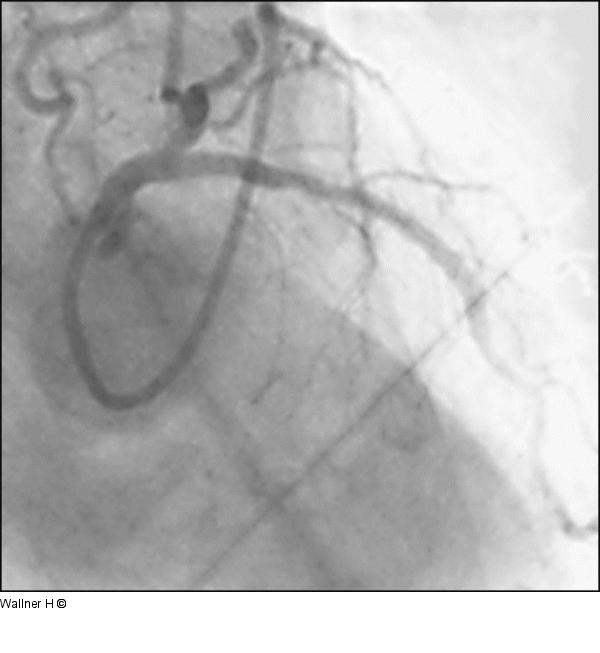

Abbildung 8: Kissing-Ballon - Mid-LAD-Stent Abschließendes Resultat nach Kissing-Ballon und nach Mid-LAD-Stent (initiale PCI). |

Abschließendes Resultat nach Kissing-Ballon und nach Mid-LAD-Stent (initiale PCI). |